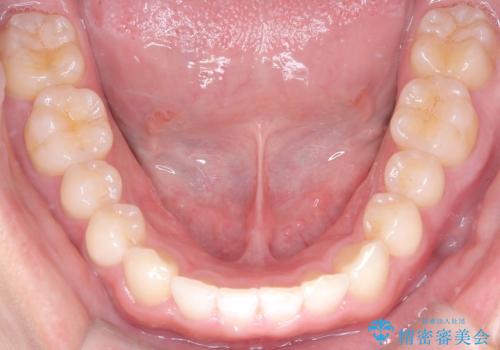

- 歯のデコボコと過蓋咬合を主訴に来院された患者様です。

アーチの拡大とIPRを行い非抜歯で治療を行いました。

歯を抜かずに叢生(デコボコ歯列)と過蓋咬合を改善する事が出来ました。